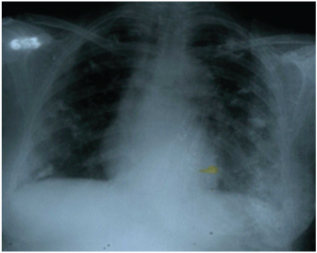

A 50-year-old female presented in Radiotherapy OPD, with an ulcerated growth in the left lumbar region associated with mild to moderate pain since one year. Patient had history of growth five year back at same site for which she underwent excision for five times in duration of five years last 11 months back of presentation. Her family, medical history was not significant. On examination, a multilobulated large well defined growth was present in the left lumbar region, measuring approximately 15 X 20 cm, with a variegated and irregular surface, fixed to underlying tissue and non tender on palpation [Table/Fig-1a,b]. Per abdomen examination was normal. There was no lymph node palpable in cervical, axillary or inguinal region. Blood investigations including renal function tests, liver function tests were normal. On serological examination patient was non reactive for Anti-HCV, HbsAg and HIV 1and 2. Ultrasonography of abdomen revealed a large heteroechoic lesion in left lumbar region with areas of necrosis at its upper pole, showing flow on color doppler seen at the site of growth and there was no lymphadenopathy. MRI abdomen revealed large soft tissue mass with lobulated margin, of size approximately 127 mm X 113 mm X 149 mm seen in subcutaneous plane of left posterior and left lateral aspect. The lesion appeared hypointense on T1W, of mixed intensity on T2W images and hyperintense on STIR images. It caused a compression effect on paraspinal and abdominal muscles. Scoliosis with convexity towards left side was also seen in lumbar region [Table/Fig-2a,b]. Chest X- ray revealed multiple non homogenous opacity in bilateral lung fields [Table/Fig-3]. With the above findings, a provisional radiological diagnosis of soft tissue mass was made. On histopathological examination epidermis was atrophied at places. Dermis revealed a tumour which reached the overlying epidermis and infiltrated subcutaneous tissue at places. Tumour was composed of oval to spindle shaped cells arranged in groups, fascicles storiform pattern [Table/Fig-4a,b] and moderate pleomorphism and few areas of haemorrhage, entrapment of fat cells [Table/Fig-4c,d] and necrosis were also seen. Immunohistochemistry of tumour was positive for vimentin [Table/Fig-5,6] and CD 34 [Table/Fig-7a,b] but negative for smooth muscle actin [Table/Fig-8]. Based on this histopathological findings and IHC markers diagnosis suggestive of Dermatofibrosarcoma protuberance was made. Due to size of the mass, the patient was given 20 Grays of external beam radiotherapy. Presently, the patient is on adjuvant chemotherapy consisting of vincristine, doxorubicin and cyclophosphamide regimen. Till date patient has completed six cycles of chemotherapy without any adverse events. The tumour and opacity in bilateral lung region reduced in size.

Chest X- ray PA view revealed multiple non homogenous opacity in bilateral lungs